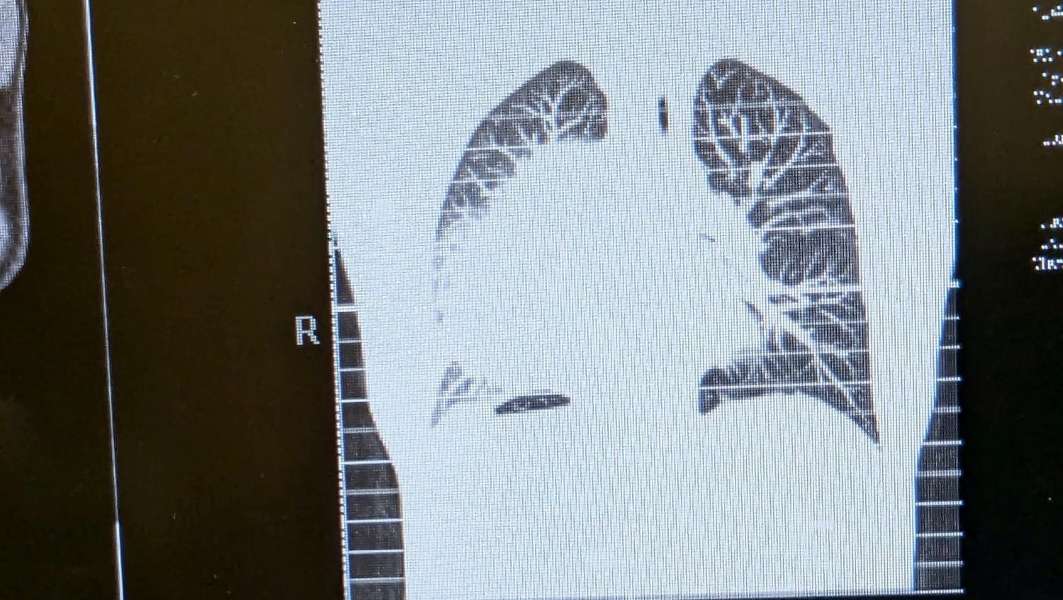

Doctors initially thought Bailey had pneumonia or tuberculosis, but after performing an X-ray and CT scan, they found a cantaloupe-sized mass in the middle of his chest. Elder Bailey's mission would suddenly come to an end as he was rushed home to eastern Idaho for life-saving treatment.

The massive tumor is uncomfortable — pressing his right lung tight against his chest to the point "you can just barely see the lining of my lung where (the tumor)'s pushing so big," he explains.

"It's growing in the lymphatic system," says Jon Bailey, Bowen Bailey's father. "Imagine this big, massive mass, probably smaller than a volleyball but a very large cantaloupe, and it's basically pushing his lung all the way to his ribs, so that there's no use of that lung."